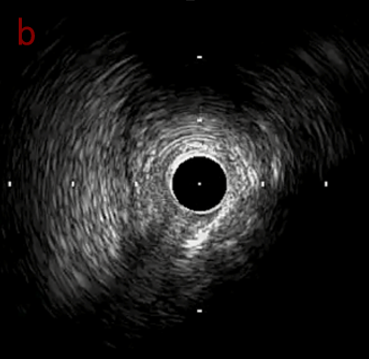

IVUS after OAS high speed 3回

IVUS imaging after high speed 3回

a,b,cはさらに石灰化に食い込み、石灰化量は減少。

それに伴いdではbiasがさらにtentingのIVUS所見にへんかしhigh injury riskと思われた。

引き続き造影で確認してpinpointで引きのOAS high speedを3回さらに追加のためcでIVUSマーキングを行い、その点より引きで赤線のpinpoint OAS high speedを行い、dに関してはinjury回避のためにOASを当てない方針とした。